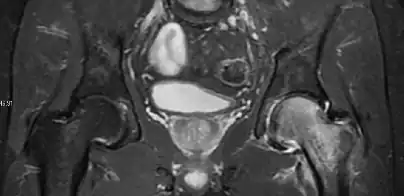

Magnetic resonance imaging

Many pathological conditions of the hip are detected early by MRI due to its high soft tissue resolution and sensitivity. Its accuracy in studying acute hip pain in children has proved to be superior to ultrasound and plan film radiography. However, MRI accessibility and the need of sedation relegate its use to selected cases in which diagnosis is not clear with less demanding techniques. These include differentiating transient synovitis from a septic arthritis or osteomyelitis, diagnosis of inflammatory joint disease or bone tumors, and early detection and follow-up of Perthes disease.[1]

In adults, MRI is currently playing a definite role in the assessment of osteoarthritis. Although traditionally belonging to the arena of radiographs, the role of MRI has been stressed after the term femoral acetabular impingement was coined in 2003. Growing interest has been focused in accurate diagnosis of the acetabular and femoral morphological abnormalities that may lead to early osteoarthritis.[1]

MR imaging is considered paramount to these objectives, mainly when surgery is considered, due to the ability of MRI to portray the whole section of the femoral neck surface, as well as to image the labrum and articular cartilage.[1]

Most of the angles and measurements described in the plain radiograph section can be accurately reproduced on MRI. In addition, the superiority of MRI resolution with intra-articular contrast allows detection of labral and chondral abnormalities that may influence the choice of medical, percutaneous, or surgical management (Figure 9).[1]

Figure 9:

-

Sagittal T1 weighted image showing anterosuperior labral tear.[1] -

Sagittal T1 weighted image showing chondral lesion.[1] -

Sagittal CT-arthrography showing posteroinferior chondral injury.[1] -

Coronal CT-arthrography (d) showing ligamentum teres tear.[1]

MR arthrography has proven superior in accuracy when compared to native MR imaging. It is considered the best technique to assess the labrum. Knowledge of the normal variable morphology of the labrum helps to differentiate tears from normal variants. A triangular shape is most commonly seen in 66% of asymptomatic volunteers, but round, flattened, and absent labra can also be found in asymptomatic populations. MR arthrography has demonstrated sensitivity over 90% and specificity close to 100% in detecting labral tears. Loose bodies are demonstrated as filling defects surrounded by the hyperintense gadolinium.[1]

Association between labral tears and chondral damage has been demonstrated. This underscores the interaction between cartilage and labrum damage in the progression of osteoarthritis. Chondral damage to the posteroinferior part of the acetabulum as a contrecoup lesion occurs in approximately one-third of pincer cases secondary to persistent abutment on the anterior part of the joint leading to a slight posteroinferior subluxation. This is considered a bad prognosis sign.[1]

MR arthrography can also demonstrate ligamentum teres rupture or capsular laxity, which are debated causes of microinstability of the hip. Elongation of the capsule or injury to the iliofemoral ligament or labrum may be secondary to microtrauma in athletes. MR can demonstrate abnormalities in these cases, such as increased joint volume or a ligamentum teres tear (Figure 9).[1]